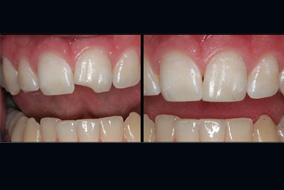

Conservative Dentistry &  Endodontics Department :

• Treatment (RCT)

• Aesthetic filling for broken tooth

• Cosmetic filling or tooth colour matching filling

• Emergency Dental pain management